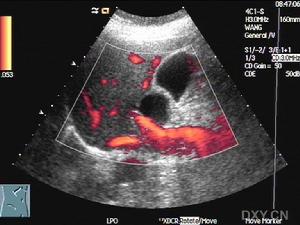

膽囊息肉超聲圖示(3)腺瘤樣增生、腺肌瘤:腺瘤樣增生是一種由於膽囊上皮和平滑肌增生而引起的膽囊壁肥厚性病變,分為3型:

1.B超檢查方法靈活、準確、無創傷、可重複、價廉、易為眾多患者接受,能準確地顯示息肉的大小、位置、數量、囊壁的情況。B超典型的表現為膽囊壁有點狀、小塊狀、片狀的強或稍強回聲光團,其後多無聲影,可見到球狀、桑葚狀、乳頭狀及結節狀突出,甚至可顯示出息肉的蒂。楊漢良等報導B超對PLG檢出率為92.7%,特異性94.8%,假陽性5.2%,準確性明顯高於CT,認為BUS能清晰地顯示PLG的部位、大小、數目及局部膽囊壁的變化,是一種簡便可靠的診斷方法。2.三維超聲成像可使膽囊具有空間方位的立體感,透聲性好,有直視膽囊剖面的效果,可彌補二維顯像某些不足。不僅可觀察膽囊息肉的大小形態,更可分清息肉和膽囊壁的關係,尤其在膽囊後壁的息肉二維顯像常不能清楚地分辨是否有蒂以及蒂與膽囊壁附著的範圍和深度。三維重建能通過不同切面的旋轉來觀察病變的連續性及病變表面的情況等信息,有助於提高膽囊息肉與膽囊腺瘤或癌腫的鑑別。王連生等報導用三維超聲成像檢查18例膽囊內病變,最大直徑為5.5cm,最小直徑0.3cm,其中5例為多發性息肉,9例為單發性息肉,4例膽囊癌均為多發占位病變。三維超聲成像與術中所見基本一致。

膽囊息肉影像圖示1.彩色都卜勒超聲在腫塊內和膽囊壁內出現高速動脈血流信號,是原發性膽囊癌區別於良性腫塊和轉移癌的重要鑑別特徵。如膽固醇性息肉血流為直線狀,<20cm/s;而膽囊癌內血流多呈樹枝狀,流速>20cm/s。RI越小越傾向於惡性,但對於早期膽囊癌腫塊過小者(<3mm)有時並不敏感,此外還與操作者技術水平有重要關係。